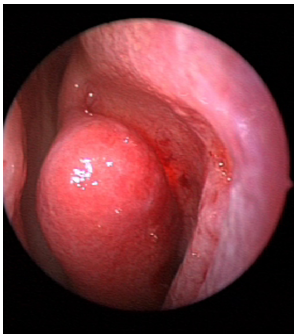

During the surgical procedure the use of a rigid light probe inserted in the inferior lacrimal punctum and canaliculus allows identifying the projection of the lacrimal sac on the lateral nasal wall (Figure 1). In fact, the site of major illumination helps the operator in defining where the bone is thinnest in the lacrimal fossa. This technique further confirms the relation between UP and lacrimal bone, already evaluated with CT. As shown in Figure 2, the prelacrimal UP hides the lacrimal bone making its removal necessary in order to realize the ostomy with the lacrimal sac.

Figure 2 Left nostril – transillumination of the lacrimal sac impeded by pre-lacrimal insertion of UP.